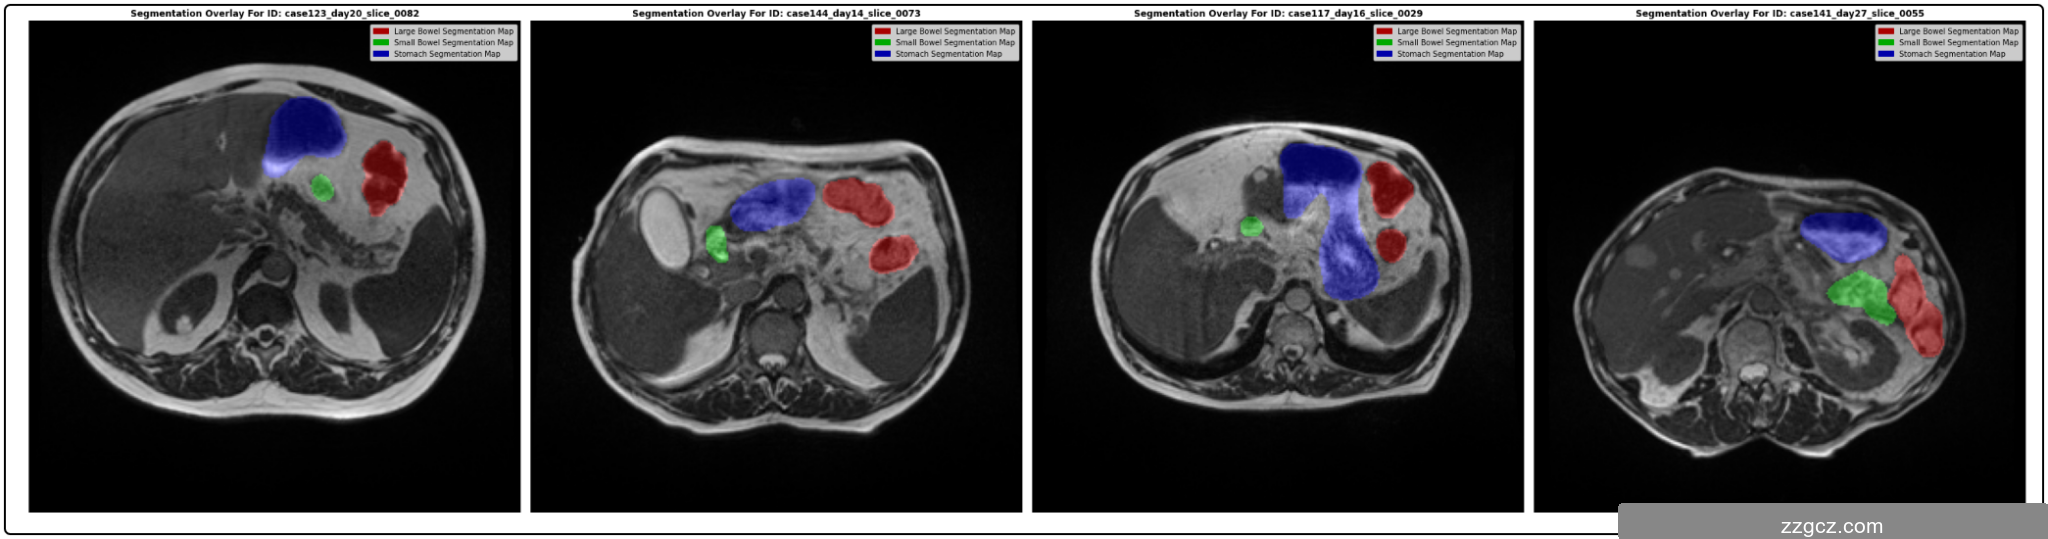

本项目基于A052-SegFormer模型实现医学影像图像分割,旨在提供一种高效且精准的分割方案以满足临床和研究中的图像处理需求。医学影像分割是医疗领域中的一个关键任务,它能够辅助医生进行疾病的精准诊断和分析,例如器官或病灶的定位与形态判断。传统的分割方法依赖手工设计特征或简单的阈值分割,无法处理复杂的结构和形态,而深度学习模型凭借其强大的特征提取和学习能力,可以自动从数据中提取多层次的信息表示。本项目中采用了SegFormer模型,这是一种基于Transformer的图像分割架构,结合了卷积神经网络和Transformer的优点,通过多尺度特征提取和自注意力机制能够有效捕捉医学图像中不同尺度下的特征信息,从而提升分割性能。该模型使用轻量化设计,具有较低的计算开销和内存需求,非常适合应用于资源受限的场景,如实时诊断系统和便携式医疗设备。项目的主要目标是验证SegFormer在医学图像数据集上的分割性能,并通过对比实验和可视化展示其在精度和效率方面的优势,为实际应用提供理论支持和算法参考。

3. 数据集与预处理

本项目使用的医学影像数据集来源于UW-Madison胃肠道(GI Tract)分割数据集。该数据集主要包含不同患者的腹部CT或MRI图像,并标注了三类主要解剖结构:小肠、大肠和胃。数据集中每个样本包含原始的影像图像(通常是灰度图或RGB图像)以及对应的分割掩码图像(标记不同器官的像素区域)。该数据集的特点是类别不平衡明显,某些器官的像素数量远多于其他类别,这在分割任务中可能导致模型对少数类别的识别能力不足。